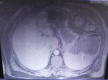

Necrobiosis lipoidica is an idiopathic dermatosis of unknown origin, occurring mainly in patients with diabetes. Splenic abscesses are rare entities. We report a case with concomitant necrobiosis lipoidica and splenic abscess. A 58-year-old man presented to emergency center with a two day history of left upper abdominal pain, general malaise, and pyrexia. On both lower legs the patient had skin lesions. The contrast-enhanced computed tomography of the abdomen revealed splenomegaly and splenic abscess in the upper pole of the spleen. On the fourth day after admission, patient underwent open splenectomy. For the lesions on lower legs, by clinical examination, necrobiosis lipoidica was confirmed. The patient was treated by topical administration of steroid cream. After a 2 months follow-up, this treatment was not effective. Left upper abdominal pain and pyrexia in patient with necrobiosis lipoidica may suggest splenic abscess.